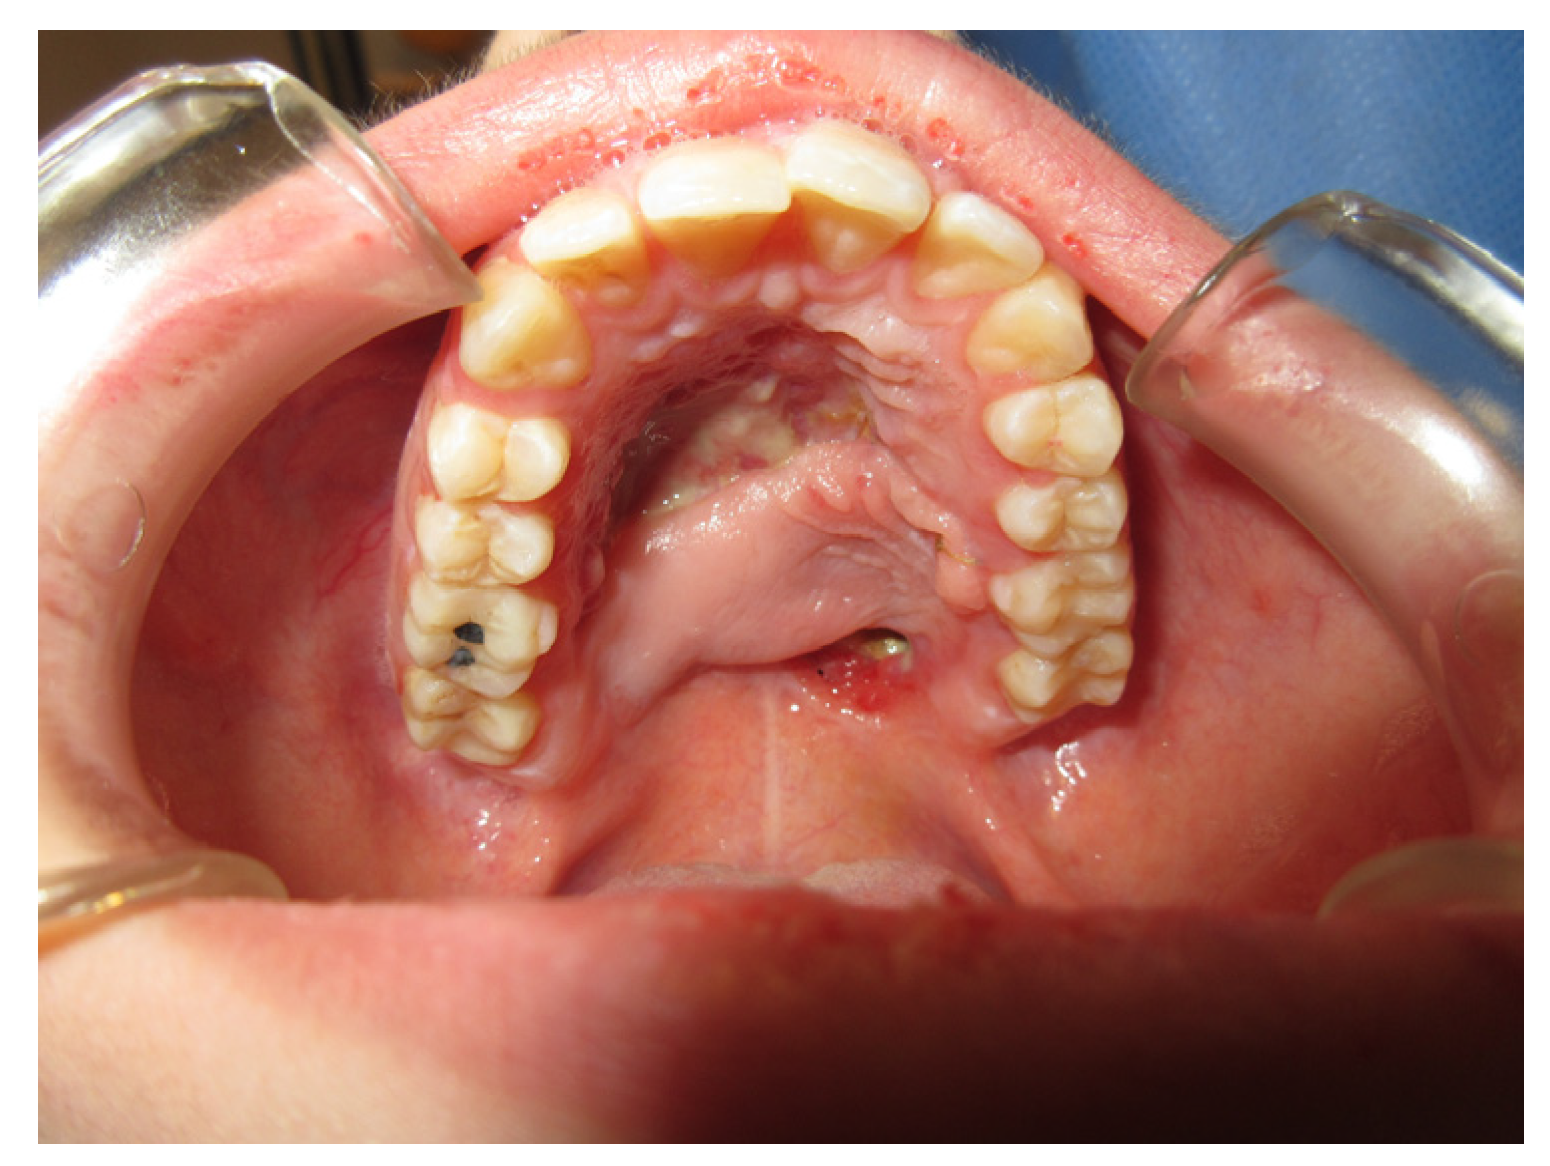

3.1.1. Case 1: A.R.

| A.R | X | * | 5 | 1 | ||